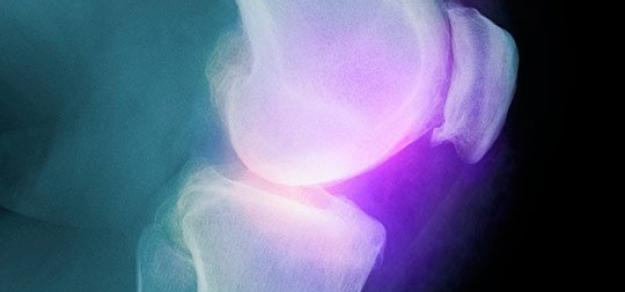

Celecoxib para artrosis. Grandes reservas en cuanto a la evidencia disponible

06 junio 2017

Cochrane Rev, 22 de mayo de 2017 Los autores tienen grandes reservas sobre los resultados debido a la participación de la industria farmacéutica y datos limitados. No se pudieron obtener los datos de tres estudios, que incluyeron 15.539 participantes, y se clasificaron como aguardando evaluación. La evidencia actual indica que el celecoxib es ligeramente mejor que el placebo y algunos AINEs para reducir el dolor y mejorar la función física, Esta mejora puede no ser clínicamente significativa